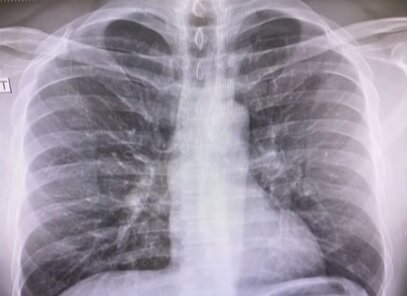

Także dodał to, że później miał wysoką gorączkę około 40 stopni. Amerykańska gwiazda postanowiła podzielić się zdjęciem swoich płuc, który zrobił podczas RTG. W prześwietleniu widzimy nagromadzony płyn.

Lekarze oczekują ode mnie kontroli, ponieważ mam wirusa, i muszę ci powiedzieć – to przerażające, że twoje płuca wznoszą się tam i widzą te rzeczy i mówią: „Cóż, co to jest? Co to takiego tam pali? I mówią ci: „Tak, to wirus” - opowiadał amerykańśki dziennikarz Chris Cuomo.